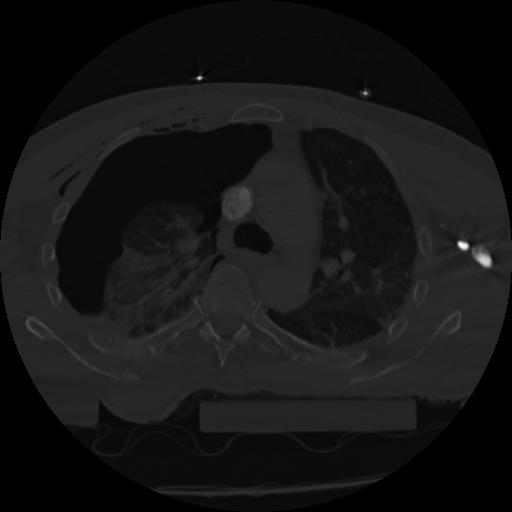

22 ANGIO,CE,Vol,0.5,ANGIO,,